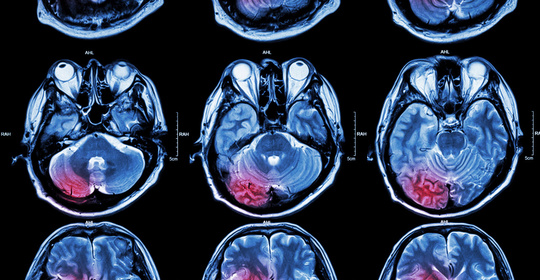

腦中風後遺症的症狀、前兆、治療和預防

腦溢血後遺症的症狀、前兆、治療和預防

腦血管破裂後遺症的症狀、前兆、治療和預防

腦梗塞後遺症的症狀、前兆、治療與預防

腦出血引流手術後遺症的症狀、前兆、治療和預防

腦栓塞後遺症的症狀表現、前兆、治療與預防